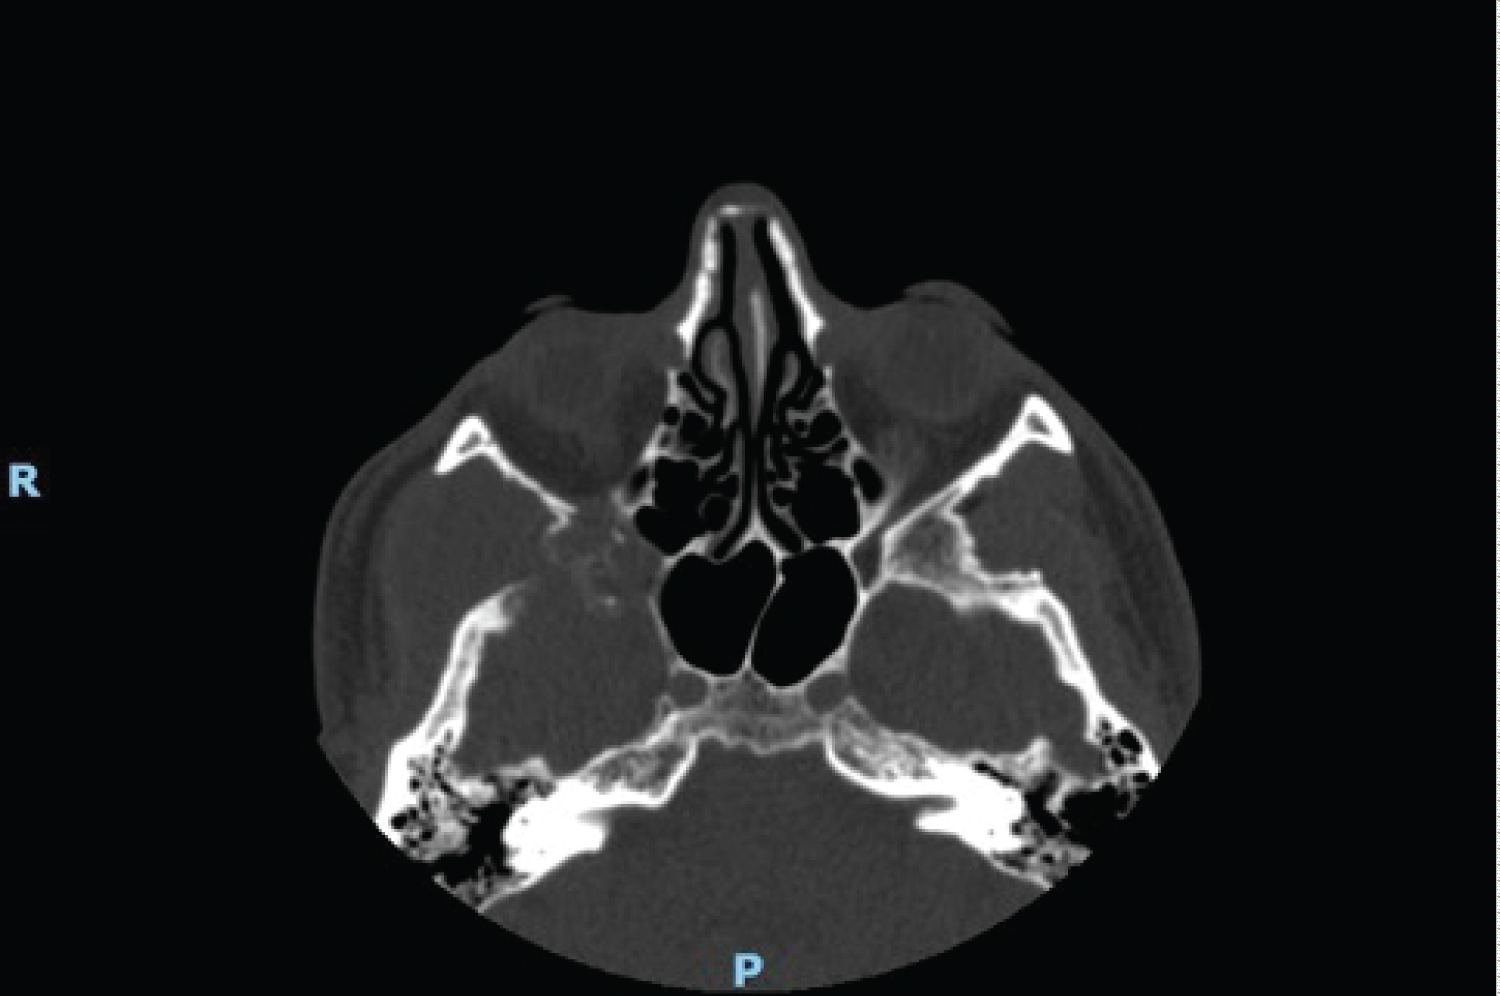

A contrast computer tomography (CT) and a Magnetic resonance imaging (MRI) were performed and revealed a 70 × 28 mm extra-axial neoplasm in the right temporal fossa up to the inferior orbital fissure. This mass came in touch with the extrinsic eye muscles causing perilesional oedema. The right temporal lobe, the right masseter and the right temporal muscle were compressed by the lesion, while the right temporal bone was eroded (Figure 1, Figure 2, Figure 3 and Figure 4).

Figure 4: CT scan, pre-operative axial image. View Figure 4